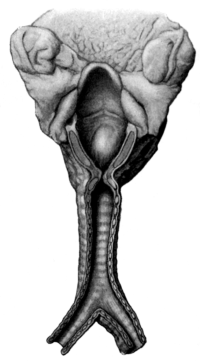

| 256. | Multiple Papillomata of the Larynx | 479 |

| 259. | Intrinsic Tumour of the Larynx | 487 |